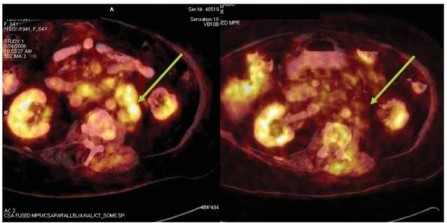

Obr. 2: Hodnocení léčebné odpovědi u nemocné s folikulárním

lymfomem pomocí 18FDG PET/CT vyšetření